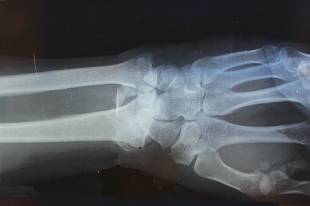

때로 뼈의 강도를 낮추어 예상 밖의 골절로 이어질 수 있습니다. 악성 세포가 정상 골조직의 배열을 흐트러뜨리면 겉으로는 버티는 것처럼 보여도 안쪽 지지력이 서서히 무너집니다. 그 결과 큰 사고가 없었는데도 금이 가거나 부러질 수 있고, 그 전부터 있던 불편이 갑자기 심해지며 상황이 드러나기도 합니다. 조용히 버티던 기둥이 어느 날 작은 흔들림에도 꺾이는 장면과 닮아 있습니다.

이런 병적 골절은 단순 외상성 골절과 달리 이전부터 이어지던 이상 신호를 함께 품고 있는 경우가 많습니다. 특별히 심한 충격이 없었는데 팔이나 다리뼈가 손상되었고, 그 전부터 같은 부위가 묵직하거나 움직일 때 불안정했다면 원인 평가가 중요합니다. 특히 성장기에는 활동량이 많아 우연한 사고로 여기기 쉬우나, 내부 구조가 약해진 상태를 놓치면 이후 치료 범위가 더 넓어질 수 있습니다.